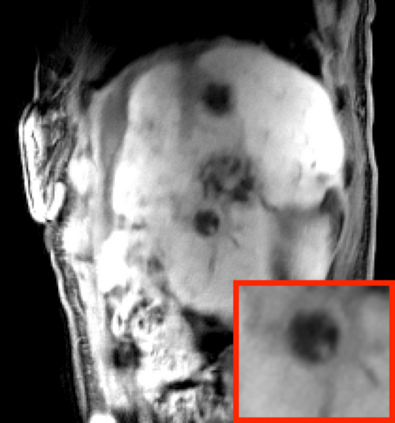

Deep neural networks for medical image reconstruction are traditionally trained using high-quality ground-truth images as training targets. Recent work onNoise2Noise (N2N) has shown the potential of using multiple noisy measurements of the same object as an alternative to having a ground truth. However, existing N2N-based methods cannot exploit information from various motion states, limiting their ability to learn on moving objects. This paper addresses this issue by proposing a novel motion-compensated deep image reconstruction (MoDIR) method that can use information from several unregistered and noisy measurements for training. MoDIR deals with object motion by including a deep registration module jointly trained with the deep reconstruction network without any ground-truth supervision. We validate MoDIR on both simulated and experimentally collected magnetic resonance imaging (MRI) data and show that it significantly improves imaging quality.